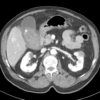

Vỡ túi mật

» Thông tin: Nam giới – 80 tuổi.

» Lâm sàng: Chấn thương.